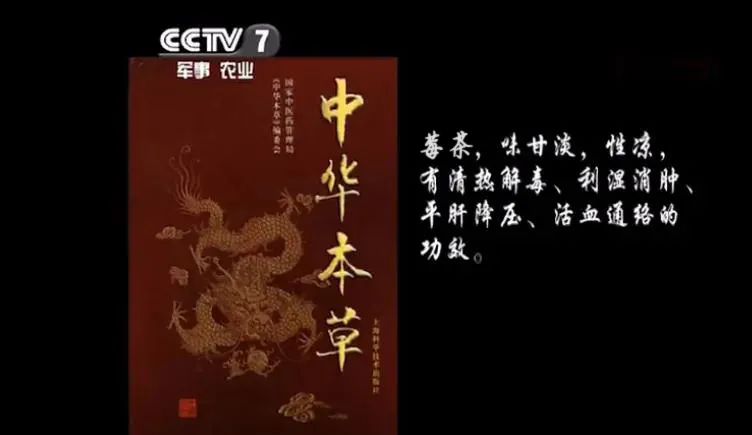

出发之前,我查了很多土家莓茶的资料,做了充分准备——